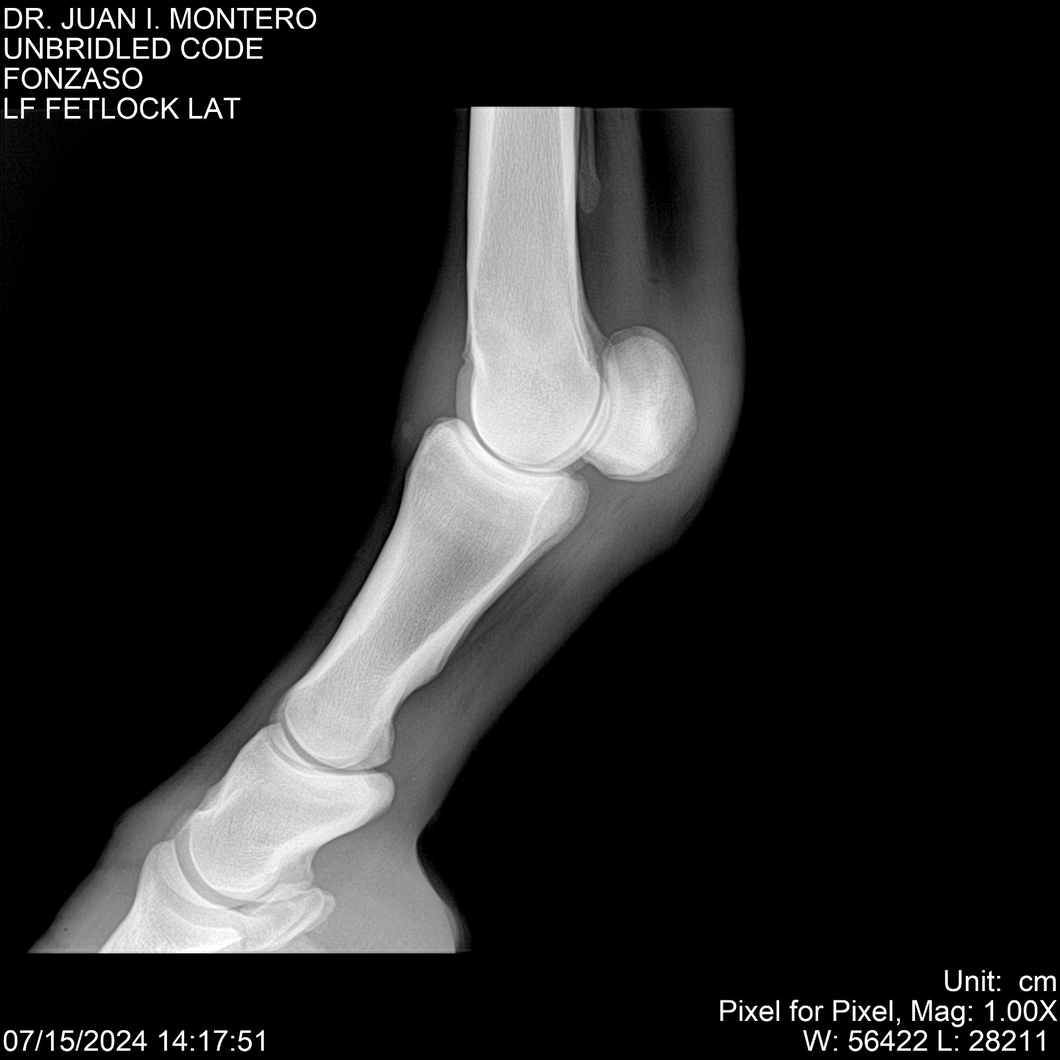

• Empresa: Abelenda N. R., Walter Hugo